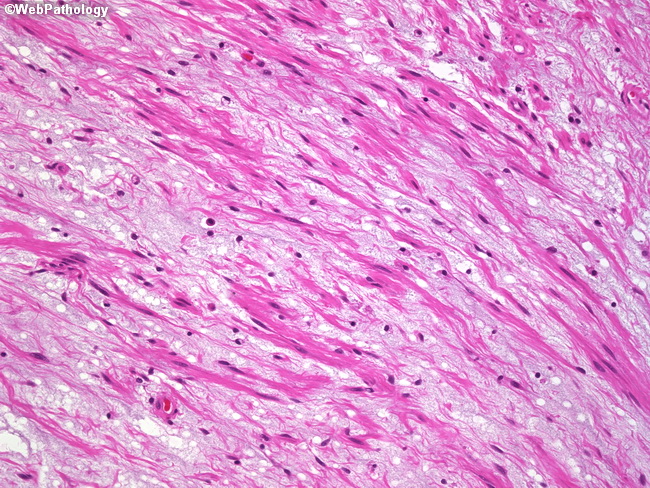

Webpathology.com: A Collection Of Surgical Pathology Images

leiomyoma myxoid change pathology webpathology comments

uterus myxoid leiomyoma muscle smooth webpathology pathology fibrillary cells nuclei comments

myxoid leiomyoma smooth cells muscle